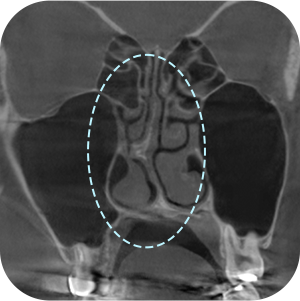

确认之前手术 的假体情报

确认鼻中隔弯曲症等 功能性问题

确认目前现假体 的位置

一定要拍鼻子CT吗?

A因为是修复手术,所以要更精密地诊断!

鼻部修复手术需要彻底的分析非常重要

通过3D-CT扫描 准确的分析! - 03